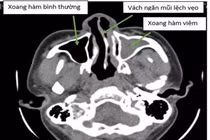

Phẫu thuật: Trong một số trường hợp, bác sĩ có thể chỉ định phẫu thuật để chỉnh sửa cấu trúc mũi hoặc họng nếu đó là nguyên nhân gây ngáy.